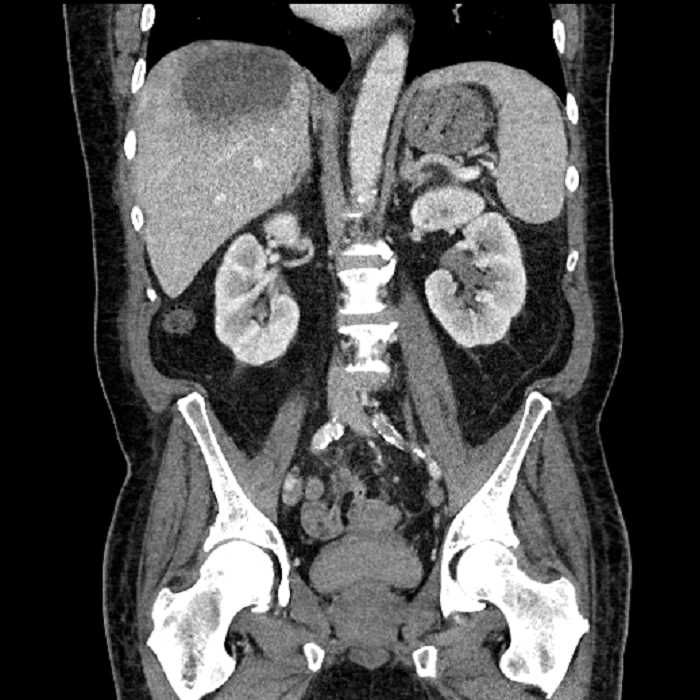

• Large fluid density structure in hepatic segments 7 and 8 measuring 10 x 7 x 7 cm with internal septation and circumferential ill-defined low density compatible with edema

• Peripherally enhancing subcapsular collections along the anterior margin of the left hepatic lobe measuring 3 x 1 cm and 2 x 1 cm

• Clearly marginated fluid density structure in segment 7 and several other scattered tiny hypodensities, which likely represent cysts

Acute sigmoid diverticulitis complicated by a small contained perforation and a large abscess in the right hepatic lobe. Additional small subcapsular abscesses along the anterior margin of the left hepatic lobe.

• The classic CT imaging appearance is a double target sign with internal low density surrounded by an internal enhancing rim (capsule) and a low density external rim (edema)

Hepatic abscess showing the double target sign with low density internally surrounded by a thin inner enhancing rim (red arrow) and ill-defined outer low density rim (yellow arrow). Blue arrow indicates an internal septation. Red arrows: additional smaller subcapsular abscesses. Red arrow: focal contained perforation associated with diverticulitis.